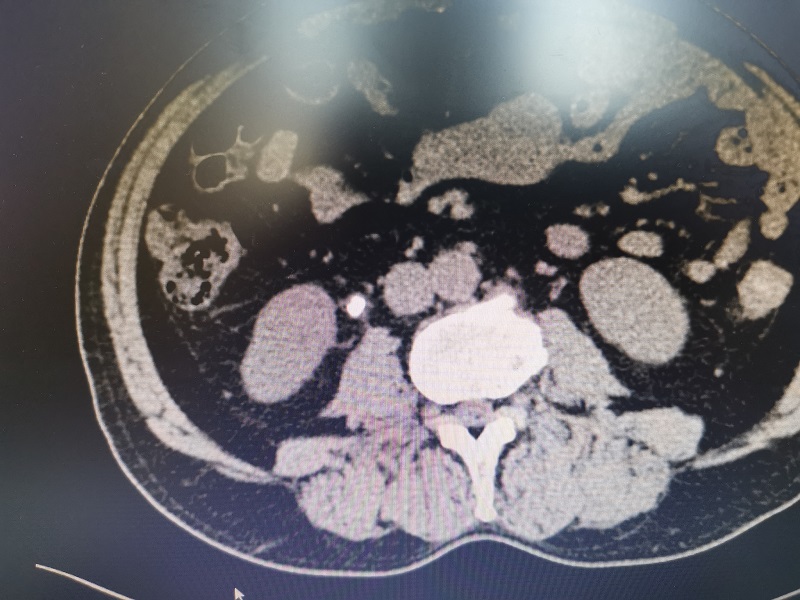

其中一例患者因“間斷右側(cè)腰部疼痛2月”入院,入院B超提示右側(cè)輸尿管上段可見一約15mm×6mm大小的強(qiáng)回聲團(tuán)塊,行CT檢查進(jìn)一步確診為輸尿管結(jié)石。因該結(jié)石大于1厘米,若行激光碎石治療,排石期長且感染風(fēng)險(xiǎn)高,經(jīng)與家屬溝通,同意行腹腔鏡下輸尿管切開取石術(shù)。